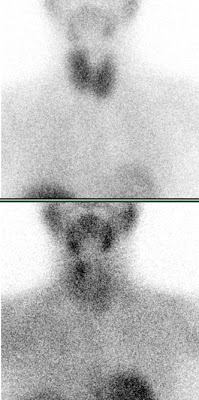

Spezialisierte Chirurgen sind in der Lage, über einen ca. 2 cm großen Schnitt Nebenschilddrüsenadenome innerhalb weniger Minuten (in Narkose) zu entfernen. Hierfür ist allerdings erforderlich, zuvor die Lokalisation mit einer Nebenschilddrüsen-Szintigraphie abzusichern. Dafür wird in der Regel Tc-99m-markiertes MIBI injiziert, das sich in den meisten Nebenschilddrüsenadenomen anreichert. Mit dieser Methode können auch ektop gelegene Nebenschilddrüsenadenome gefunden werden.